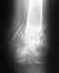

Ситуация здесь непростая. Стандартное эндопротезирование тут не годится, нужен ревизионный или онкологический протез, да и риск инфекции очень высок. Эндопротезирование коленного сустава делают и в Курганском РНЦ, где Вы уже были. Обсуждали там этот вариант?

Можно обсуждать артродез (замыкание) коленного сустава с остесинтезом длинным внутрикостным стержнем бедро-голень. Сравнительных снмков нет, еще и про укорочение то есть нет информации.